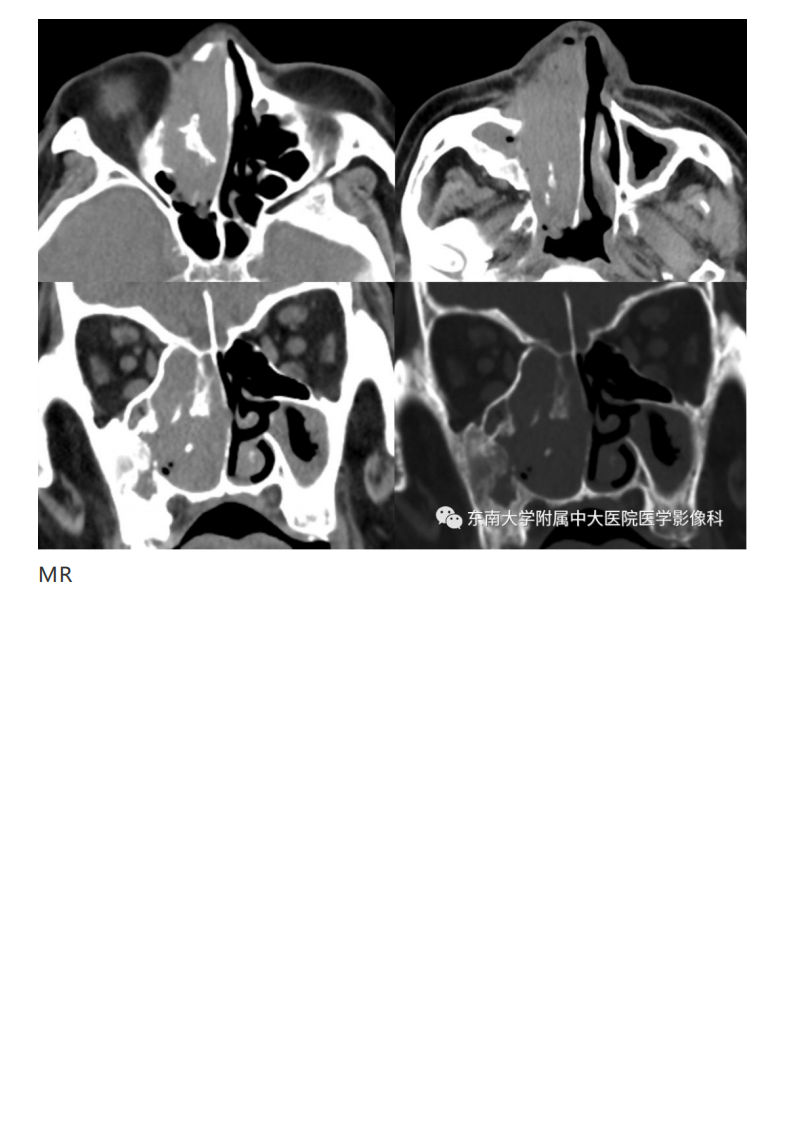

20190325_2【晨读结果公布】2019.03.25头颈部系统疾病.pdf